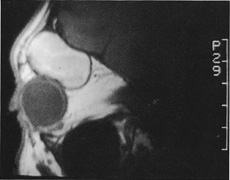

Fig. 20. A. Axial CT scan of a superonasal orbital cyst. B. Nasal extension of the superior lid crease is directed up at a right angle to the crease, toward the nasal brow. C. Incision through skin and orbicularis and superior dissection to expose and incise septum allows removal of the anterior orbital cyst.

Fig. 21. A. Sagittal MR image demonstrating a large hematic cyst in the right superior orbit. B. Lid crease incision marked across the width of the right upper lid and extending laterally toward the tail of the brow. C. Dissection plane deep to skin and orbicularis and superficial to orbital septum allows ready exposure of the supraorbital rim. D,E. Periosteum over the supraorbital rim is incised with a No. 15 blade and dissection carried out to expose the full extent of the hematic cyst (E). F. After removal of the cyst, simple skin closure is accomplished with a running absorbable suture in the lid crease. A drain is brought out through the temporal edge of the incision. G. Postoperative appearance of the patient. Excellent scar camouflage is achieved by placing the incision within the eyelid crease.